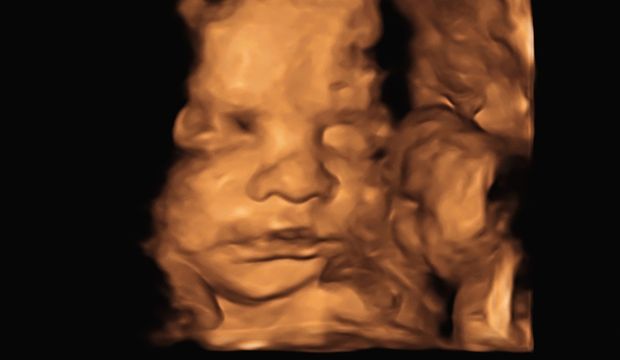

Eveett! Haftalardır beklediğim an geldi ve bebeğimi 3D olarak görebildim! Her şeyden öte detaylı ultrasonda görülebilecek tüm detaylarına baktık ve şükür herhangi bir sağlık probleminin görünmediğini, yapısal anomaliliğinin şükür ki olmadığını öğrendik. Bebeğimin gelişimi haftasıyla uyumluydu.

Açıkçası çok fazla detaya bakıldığı için öyle uzun uzun yüzünü göremedim. Bu noktada daha farklı hayal etmiştim… Tabii ki doktorum sık sık yüzünden görüntüler almaya çalıştı ancak bebeğim de buna pek izin vermedi. Sıklıkla yüzünü elleriyle kapattı ve yüzünün yarısını görebildik ama profilden görüntü alabildik. :) El parmaklarından ayak parmaklarına, beyninden kalp odacıklarına, bacak kemiğinden kulaklarına, mesanesinden dudak-damağına kadar her detaya bakıldı. Normalde ultrason görüntülerine baktığımda gördüklerimi anlamlandırabilirdim ancak her biri detaylı bakıldığı için pek anlayamadım. Zaten en önemlisi herhangi bir sağlık sorununun olmaması gerisi sadece merak ve özlem…